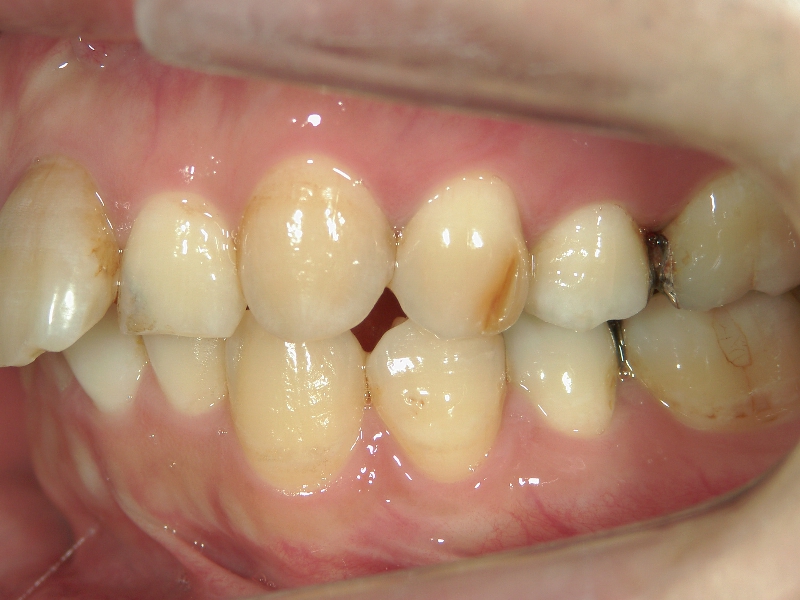

矯正歯科 治療前 上顎の左右4番計2本を抜歯し叢生を改善。

矯正歯科 治療後 E-AMXというセラミックにて左右上1番を被せ直しました。